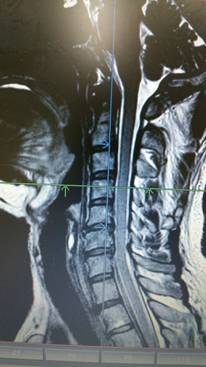

首頚椎椎間板ヘルニア専門HEADLINE

頚椎と腰椎ヘルニア 狭窄症 痛み シビレ 交通事故むち打ち治療自賠責